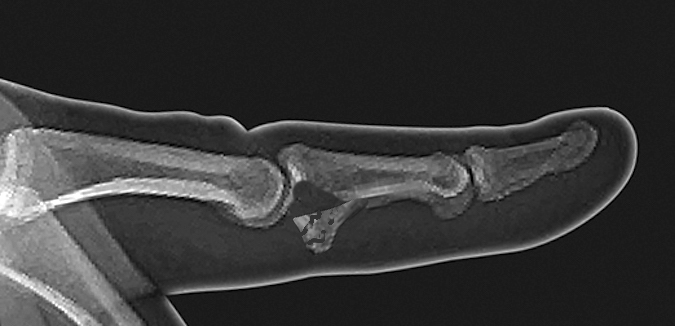

- Plain AP and true lateral X-ray views are needed.

- The X-ray will help to distinguish avulsion chip fractures from fracture-dislocations with significant PIP joint involvement.